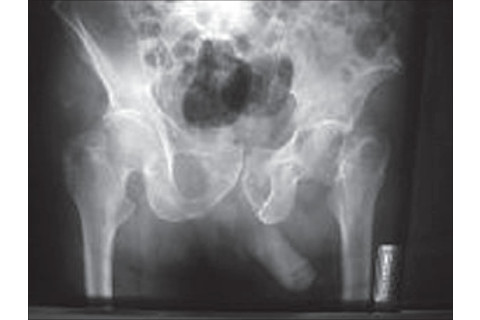

Does penis radiological shadow indicate the side of hip fracture? "Sir, Hip fractures are common injuries in the elderly. Standard radiographic evaluation of the hip includes an anteroposterior (AP) view of the pelvis. For this additional purpose, radiograph of the pelvis is one of the commonest prescribed radiographs in emergency departments. Usually we notice the fractured hip side and the type of fracture, whenever we are looking at an anteroposterior pelvis radiograph. But we do not question if this radiograph represents a true anteroposterior view. We have noticed that the radiological shadow of the penis almost always turns to the side of the hip fracture in male patients and especially in displaced fractures. Many surgeons have tried to explain this observation. So we would like to test the hypothesis that the radiological shadow of the penis indicates the side of the hip fracture. In our retrospective study, 712 male patients with hip fracture were included. In order to test our hypothesis we studied their first pelvis radiograph on admission, before operation. Intertrochanteric hip fracture was noticed in 475 cases and subcapital hip fracture in 237 cases. All the patients had no history of previous hip fracture, hip osteoarthritis, spinal cord disorders, hernia or congenital penis disorders. The mean age of the patients was 78.6 (range 68-83) years. Statistical analysis was performed by chi-square analysis. The position of patients during the anteroposterior pelvis radiograph may explain this observation. Patients with a displaced hip fracture exhibit the classic presentation of a shortened and externally rotated extremity. We believe that the patients in order to avoid further external rotation of their leg, turn their pelvis and body to the fractured side, so as to immobilize the fracture and to reduce pain. This means that the penis follows the fracture because the pelvis turns to the fractured side. So the anteroposterior view of the pelvis is in fact an oblique view, which shows the fracture and the penis shadow on the same side."